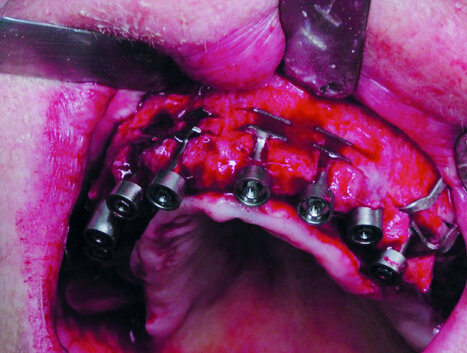

Cas 2 Indication pour une implantation bi-maxillaire. À la mandibule, préparation du lit receveur d’un implant à plaque, avec sa logette latérale vestibulaire

Cas 2b :Verrouillage de l’implant par insertion dans sa logette, et fixation à l’aide de 2 vis d’ostéosynthèse